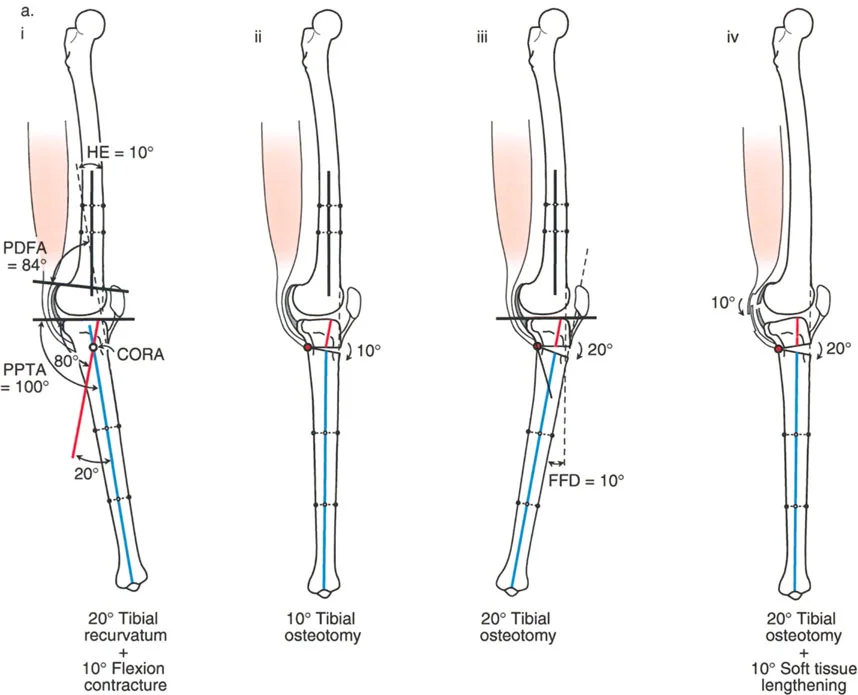

زوايا القياس الهامة:

- زاوية الانحناء البعيدة للفخذ (PDFA - Posterior Distal Femoral Angle): تقيس زاوية الجزء السفلي من عظم الفخذ. القيمة الطبيعية حوالي 84 درجة. الزيادة في هذه الزاوية (أكثر من 84 درجة) تشير إلى ارتداد فخذي.

- زاوية الانحناء القريبة للظنبوب (PPTA - Proximal Posterior Tibial Angle): تقيس زاوية الجزء العلوي من عظم الساق. القيمة الطبيعية حوالي 80 درجة. الزيادة في هذه الزاوية (أكثر من 80 درجة) تشير إلى ارتداد ظنبوبي.

- مركز دوران الزاوية (CORA - Center of Rotation of Angulation): يتم تحديد هذا النقطة على الأشعة السينية لتحديد مكان التشوه العظمي بدقة، وهو أمر بالغ الأهمية لتخطيط عملية قطع العظم.

تحليل الحالات المختلفة:

- الركبة الارتدادية بسبب الارتداد الفخذي:

- إذا كانت درجة فرط التمدد (HE) تساوي درجة الارتداد الفخذي (PDFA > 84°)، فهذا يعني أن التشوه كله ناتج عن عظم الفخذ.

- في هذه الحالة، يكون مركز CORA في الجزء البعيد من عظم الفخذ.

- إذا كانت درجة فرط التمدد (HE) تساوي درجة الارتداد الفخذي (PDFA > 84°)، فهذا يعني أن التشوه كله ناتج عن عظم الفخذ.

- الركبة الارتدادية بسبب الارتداد الفخذي مع تقلص انثناء:

- إذا كان هناك ارتداد فخذي (PDFA > 84°) ولكن لا يوجد فرط تمدد سريري (HE = 0°)، فهذا يشير إلى وجود تقلص انثناء مصاحب يعوض التشوه العظمي.

- إذا كان فرط التمدد (HE) أقل من درجة الارتداد الفخذي، فهذا يعني وجود تقلص انثناء جزئي.

- إذا كان هناك ارتداد فخذي (PDFA > 84°) ولكن لا يوجد فرط تمدد سريري (HE = 0°)، فهذا يشير إلى وجود تقلص انثناء مصاحب يعوض التشوه العظمي.

- الركبة الارتدادية بسبب الارتداد الظنبوبي:

- إذا كانت درجة فرط التمدد (HE) تساوي درجة الارتداد الظنبوبي (PPTA > 80°)، فهذا يعني أن التشوه كله ناتج عن عظم الساق.

- في هذه الحالة، يكون مركز CORA في الجزء القريب من عظم الساق.

- إذا كانت درجة فرط التمدد (HE) تساوي درجة الارتداد الظنبوبي (PPTA > 80°)، فهذا يعني أن التشوه كله ناتج عن عظم الساق.

- الركبة الارتدادية بسبب الارتداد الظنبوبي مع تقلص انثناء:

- إذا كان هناك ارتداد ظنبوبي (PPTA > 80°) ولكن لا يوجد فرط تمدد سريري (HE = 0°)، فهذا يشير إلى وجود تقلص انثناء مصاحب.

- إذا كان فرط التمدد (HE) أقل من درجة الارتداد الظنبوبي، فهذا يعني وجود تقلص انثناء جزئي.

- إذا كان هناك ارتداد ظنبوبي (PPTA > 80°) ولكن لا يوجد فرط تمدد سريري (HE = 0°)، فهذا يشير إلى وجود تقلص انثناء مصاحب.

2. العلاج الجراحي: قطع العظم (Osteotomy)

الهدف من جراحة قطع العظم هو إعادة محاذاة العظام وتصحيح التشوه الزاوي في المستوى السهمي، لاستعادة وظيفة الركبة الطبيعية واستقرارها.

أ. قطع العظم الفخذي لتصحيح الارتداد الفخذي:

- متى يتم إجراؤها: عندما يكون التشوه الرئيسي في عظم الفخذ البعيد.

- الإجراء: يتم إجراء قطع للعظم (عادة قطع عظم انثناء) في الجزء البعيد من عظم الفخذ، عند مركز دوران الزاوية (CORA)، لإعادة محاذاة العظم.

- الهدف: تصحيح فرط تمدد الركبة واستعادة المحاذاة الطبيعية.

- مثال: لتصحيح ارتداد فخذي بمقدار 20 درجة، يتم إجراء قطع عظم انثناء فخذي بمقدار 20 درجة.